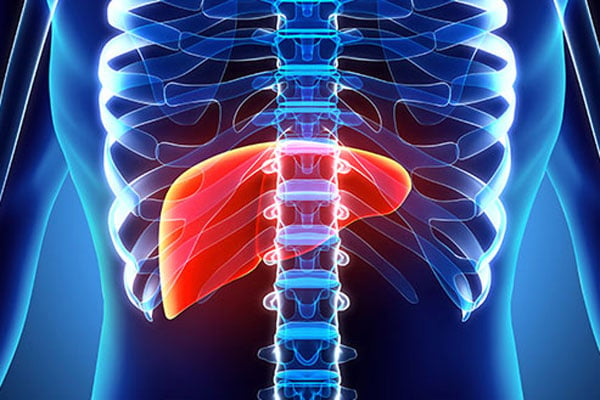

শরীরের একটি গুরুত্বপূর্ণ অঙ্গ লিভার। কিন্তু বর্তমানে অনেকেই লিভার সমস্যায় আক্রান্ত হচ্ছেন। দেহের লিভার অনেকগুলো গুরুত্বপূর্ণ কাজের সঙ্গে জড়িত। যেমন-হজম শক্তি, রোগ প্রতিরোধ ক্ষমতা বৃদ্ধি ও দেহের পুষ্টির যোগান দিয়ে থাকে। এজন্য সুস্থ থাকতে চাইলে লিভারের যত্ন নিতে হবে।